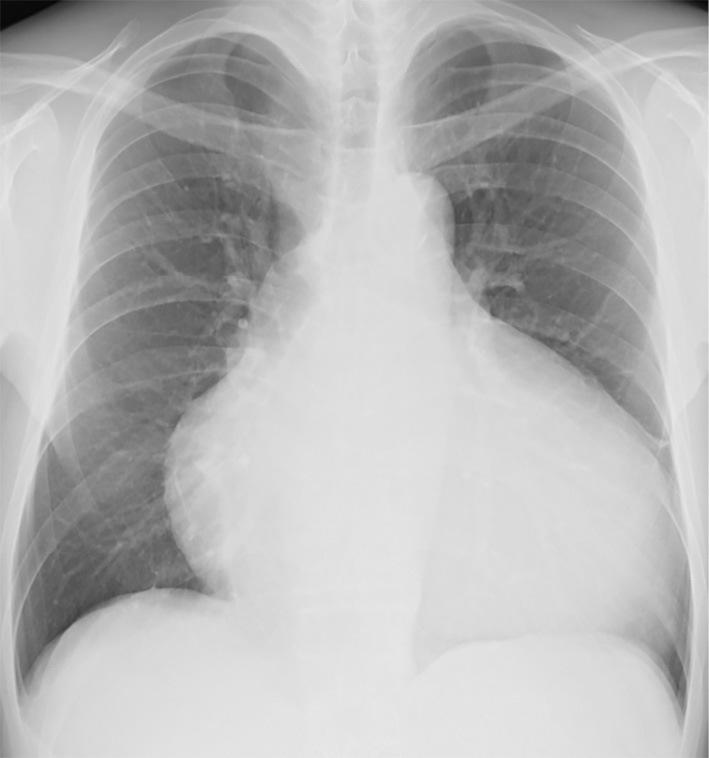

Skin abnormalities are often indicative of cardiovascular diseases. Such a disease entity is called cardiocutaneous syndrome; however, the details regarding the involvement of bulla and nails remain largely unclear. A 49-year-old man with systemic bulla was admitted for heart failure. His bulla had previously been diagnosed as epidermolysis bullosa, but no known gene mutations for it had been identified. He had a triad of palmoplantar keratosis, curly and fine hair, and cardiomyopathy, which are characteristic of NAXOS-Carvajal syndrome. This case highlights the fact that bulla and brittle nails can accompany NAXOS-Carvajal syndrome, showing that these extra-cardiac findings can help identify otherwise overlooked serious cardiac conditions.

皮肤异常常提示心血管疾病。有一种疾病实体称为心皮综合征;然而,关于水疱和指甲的具体参与情况仍不清楚。一名 49 岁男性因心力衰竭入院,全身有大疱。他的水疱先前被诊断为大疱性表皮松解症,但没有发现已知的基因突变。他患有三联征:掌跖角化过度、卷发和细软毛发以及心肌病,这是 NAXOS-Carvajal 综合征的特征。该病例强调了水疱和脆弱指甲可伴随 NAXOS-Carvajal 综合征发生的事实,表明这些心脏外表现有助于识别否则可能被忽视的严重心脏疾病。